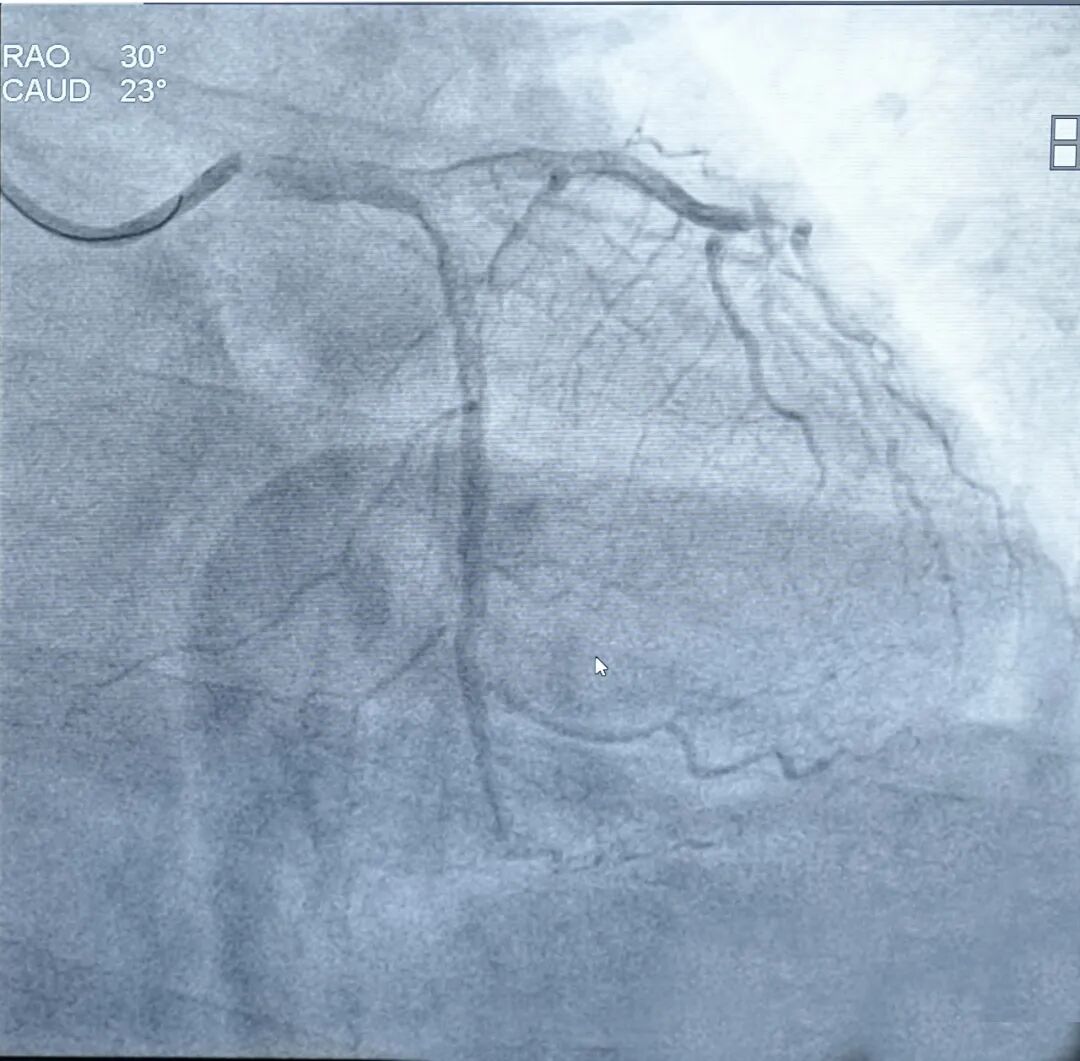

阜外医院术者为宋雷教授,病例为复杂三支病变,右冠、回旋支及前降支均存在病变,此前已完成右冠与回旋支治疗,本次处理前降支开口病变,狭窄超80%。在多支病变背景下,开口病变对定位精度与释放一致性要求极高,细微偏差都可能影响预后,整体手术容错率较低。术者操控机器人完成高难度操作:使用7F导引导管挂左冠,通过机器人精准实施双导丝技术,分别置入前降支与回旋支;随后由机器人流畅推送IVUS导管至中远端完成评估,并依次完成预扩球囊、支架及后扩球囊推送。术后复查IVUS发现局部未充分撑起,机器人随即完成精准补充后扩,最终造影显示效果良好,体现了系统在复杂背景下的精细处理能力。